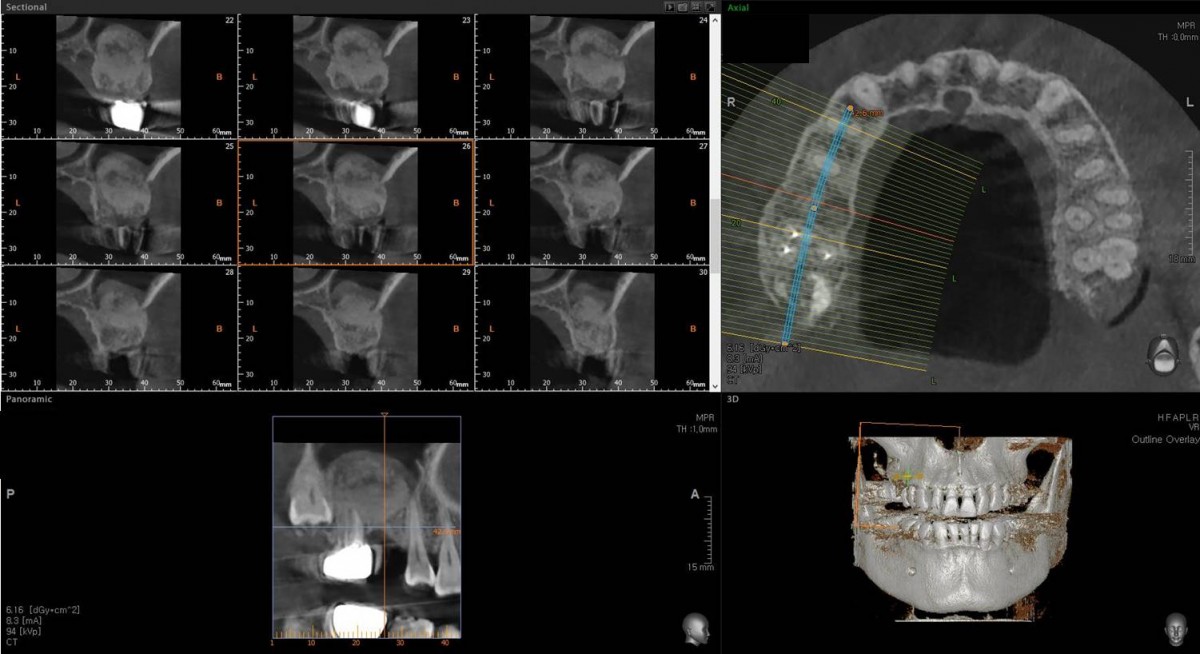

Maxillary Sinus Graft, 2 Implants, Crown Contouring

<GCaks> A 56-year-old male patient had pain-inducing caries, and perio-involved tooth mobility resulted in a tooth fracture at 1st molar. And it was removed months ago. He was a heavy smoker and showed poor oral hygiene.